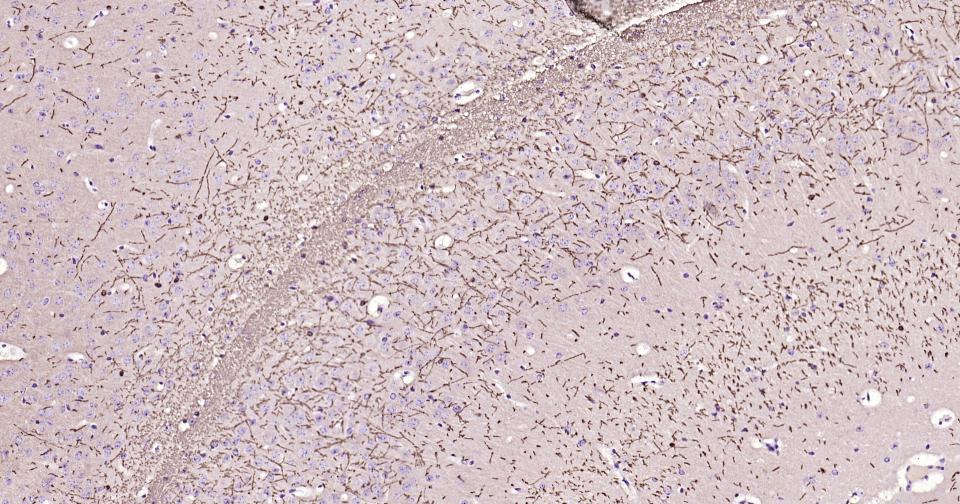

Paraformaldehyde-fixed, paraffin embedded Mouse Cerebrum; Antigen retrieval by boiling in sodium citrate buffer (pH6.0) for 15 min; Antibody incubation with MBP Monoclonal Antibody, Unconjugated(bsm-61377R) at 1:200 overnight at 4°C, followed by conjugation to the bs-0295G-HRP and DAB (C-0010) staining.